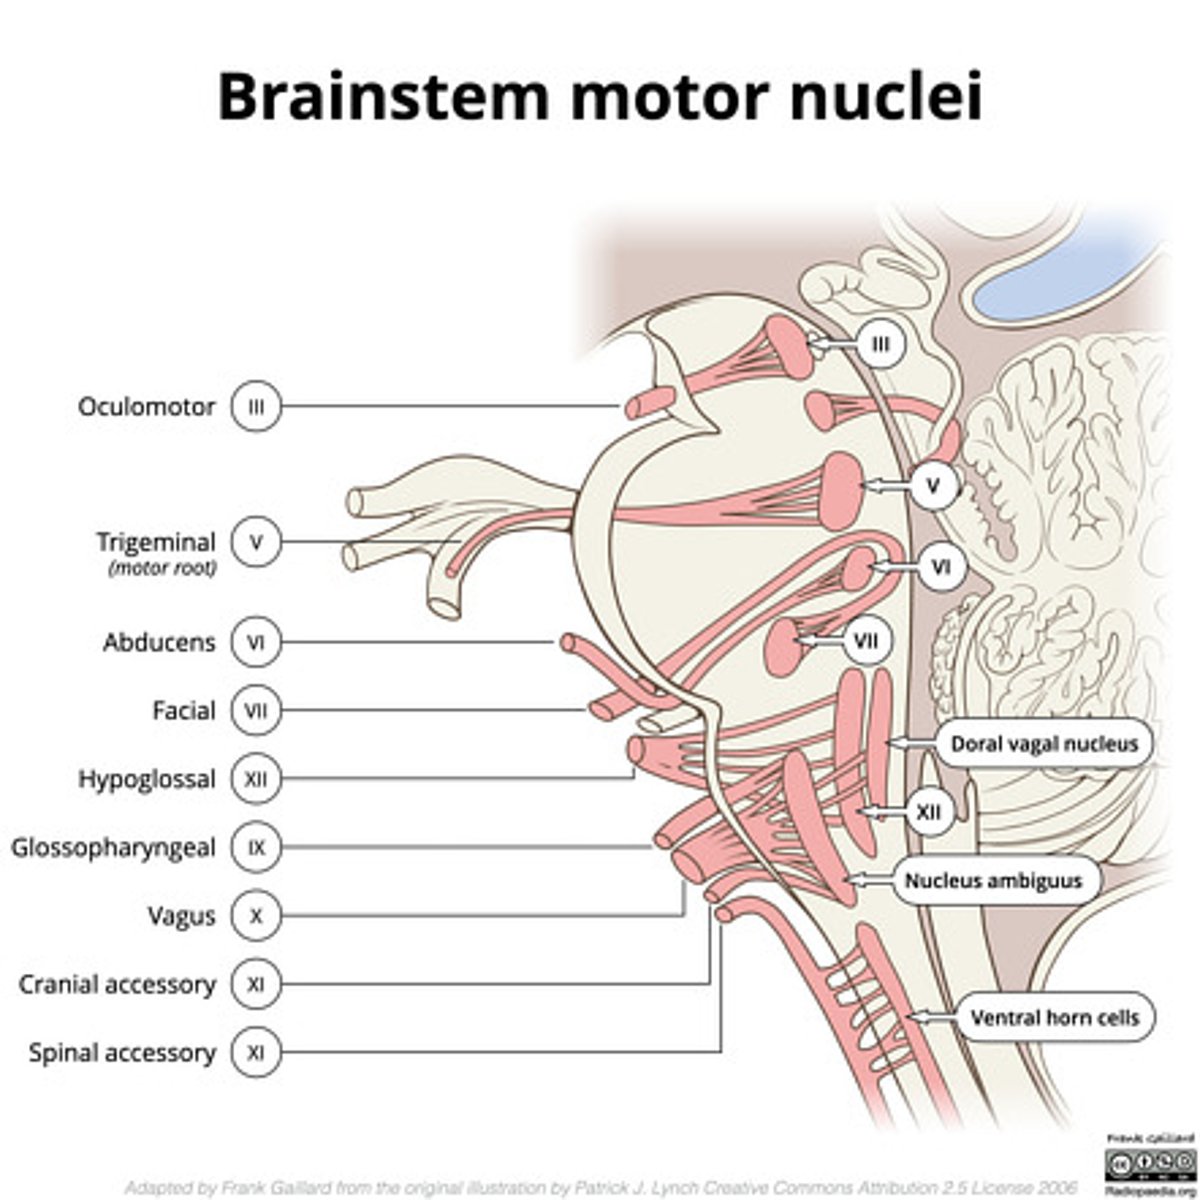

What nuclei are at the pontomedullary junction?

1. SVE of CN VI

2. SVE of CN VII (facial)

What are the facial colliculi?

bumps (hills) coming out from dorsal pontomedullary junction into the 4th ventricle -- CN VII SVE fibers create this space when they wrap around the abducens nucleus

Where do CN VI, VII, VIII exit the pons?

pontomedullary junction

What is the spacing of CN VI, VII, and VIII exiting the pontomedullary junction?

8 & 7 -- lateral and closer together

6 -- medial and far away

image -- look at red font